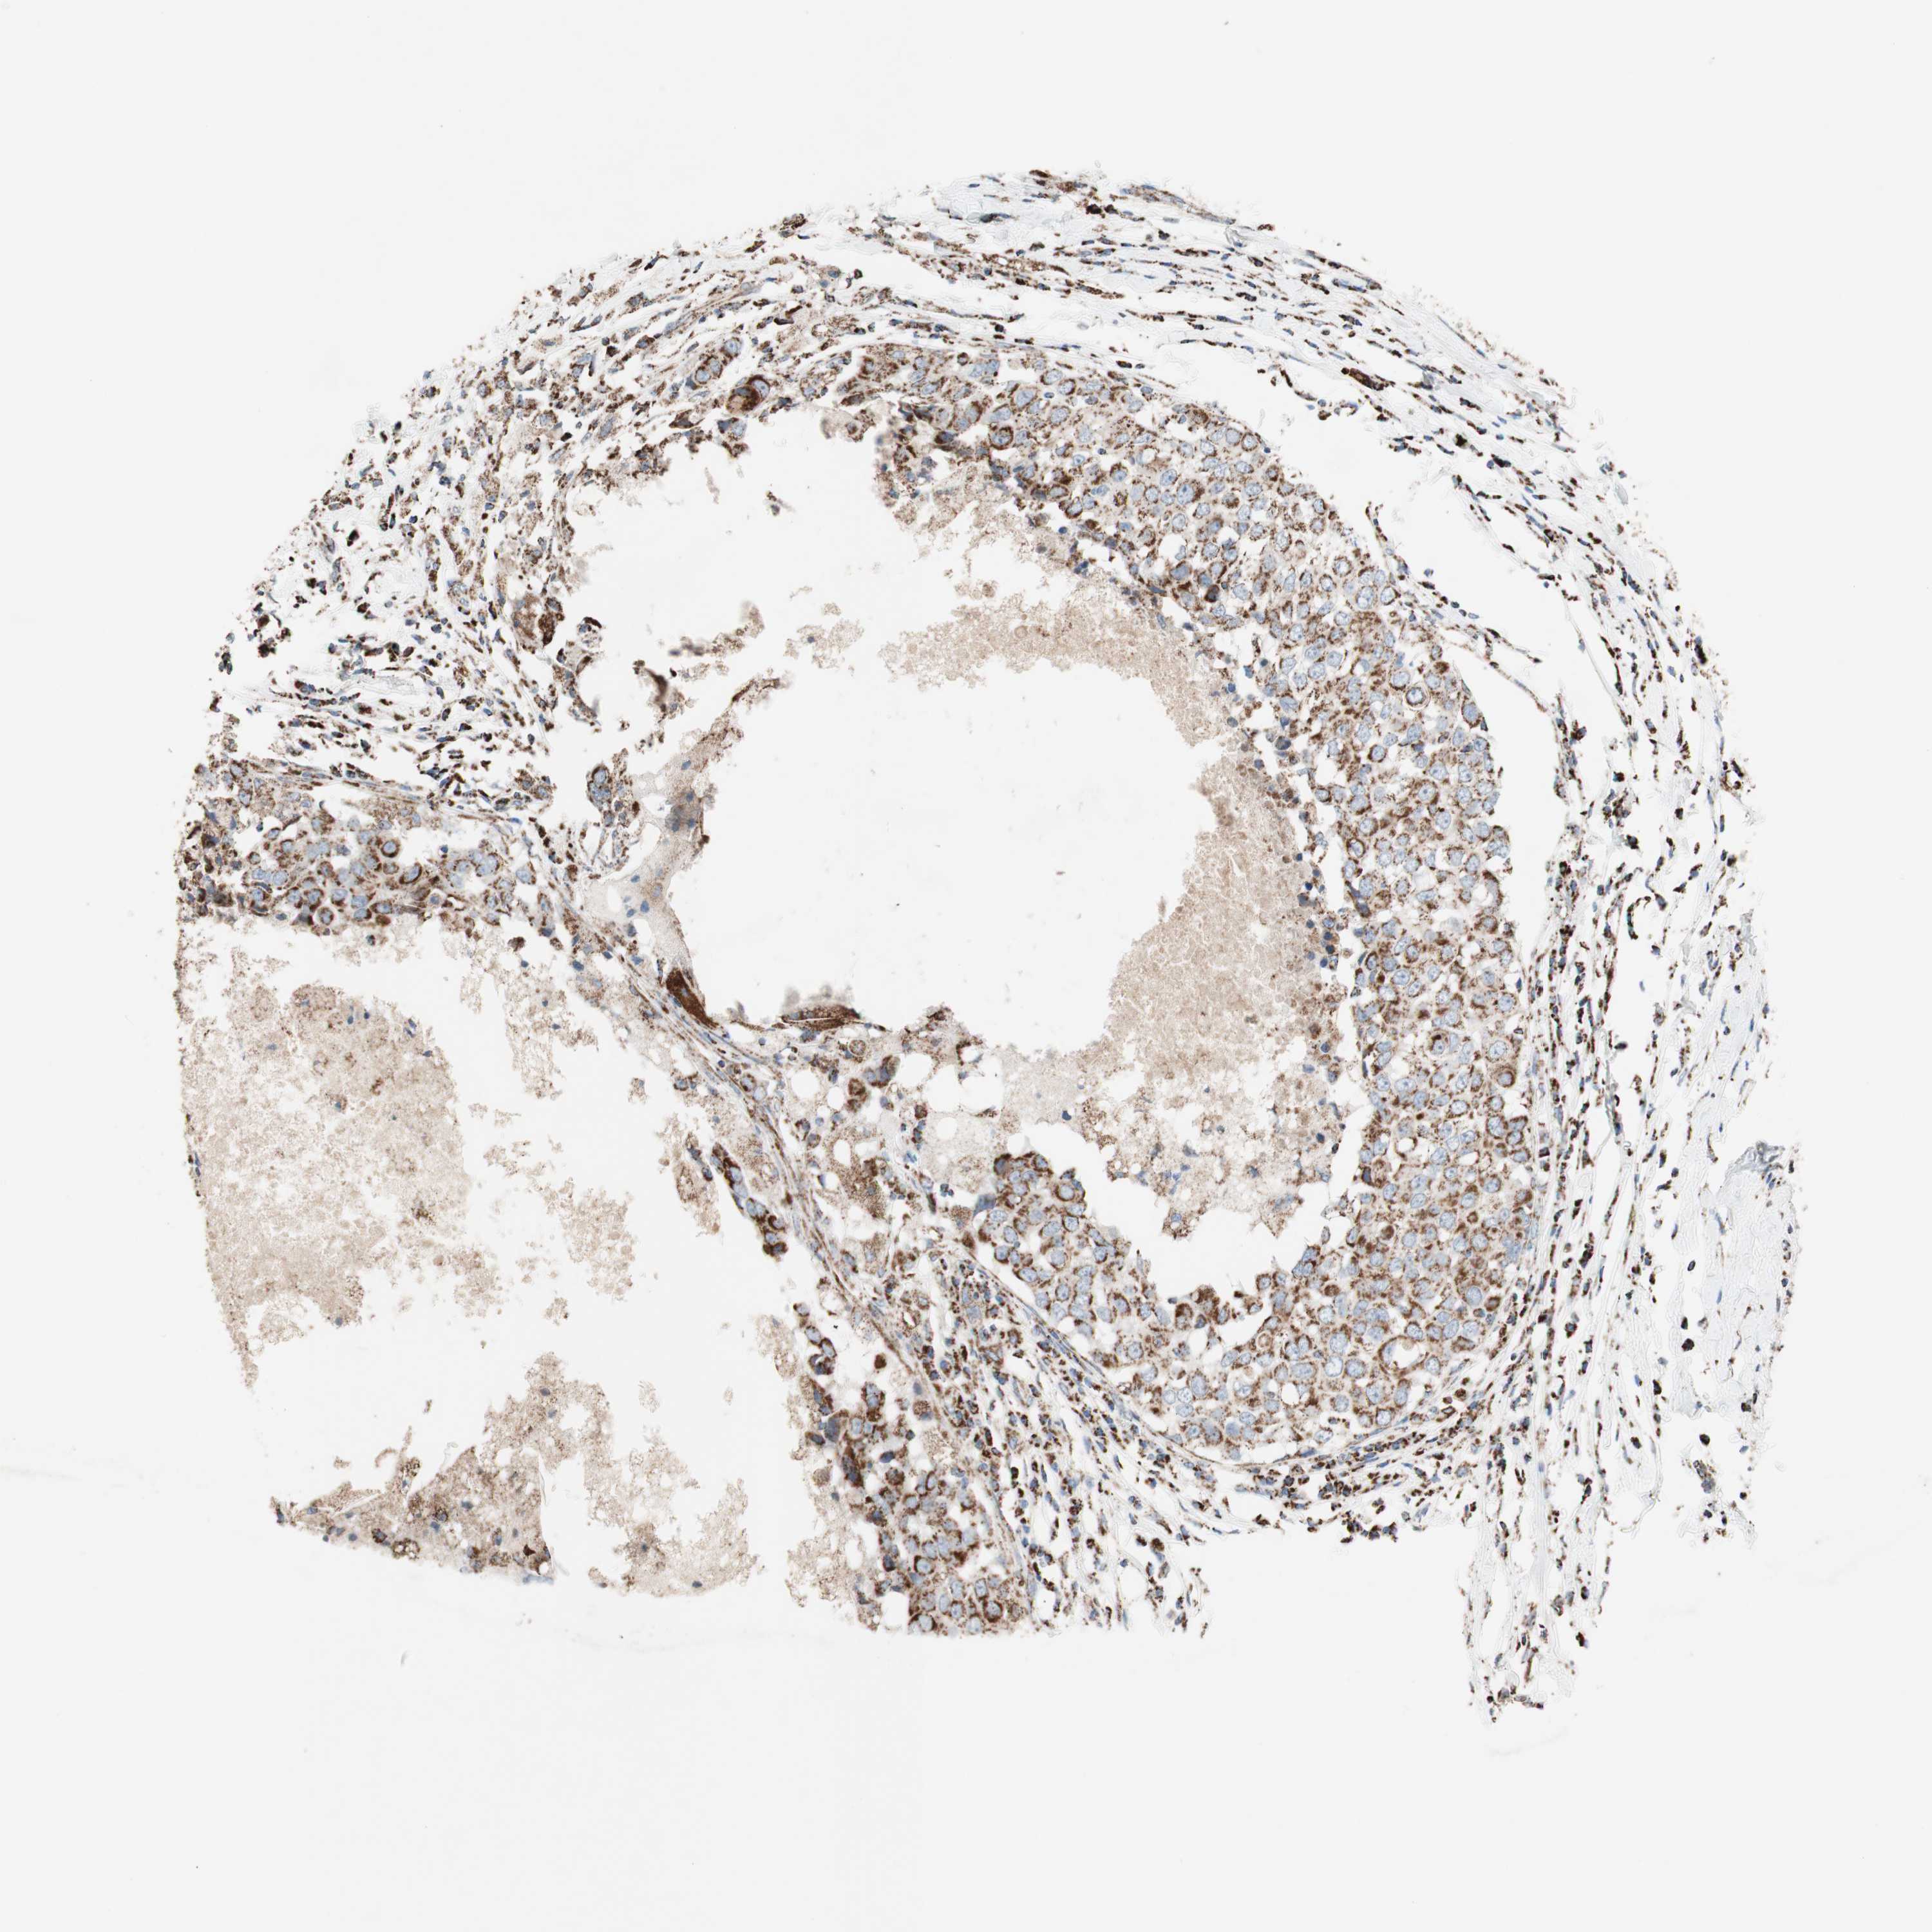

CANCER BREAST CANCER Show tissue menu

BRCA TCGA BRCA VALIDATION PROTEIN EXPRESSION

ANTIBODIES

AND

VALIDATION